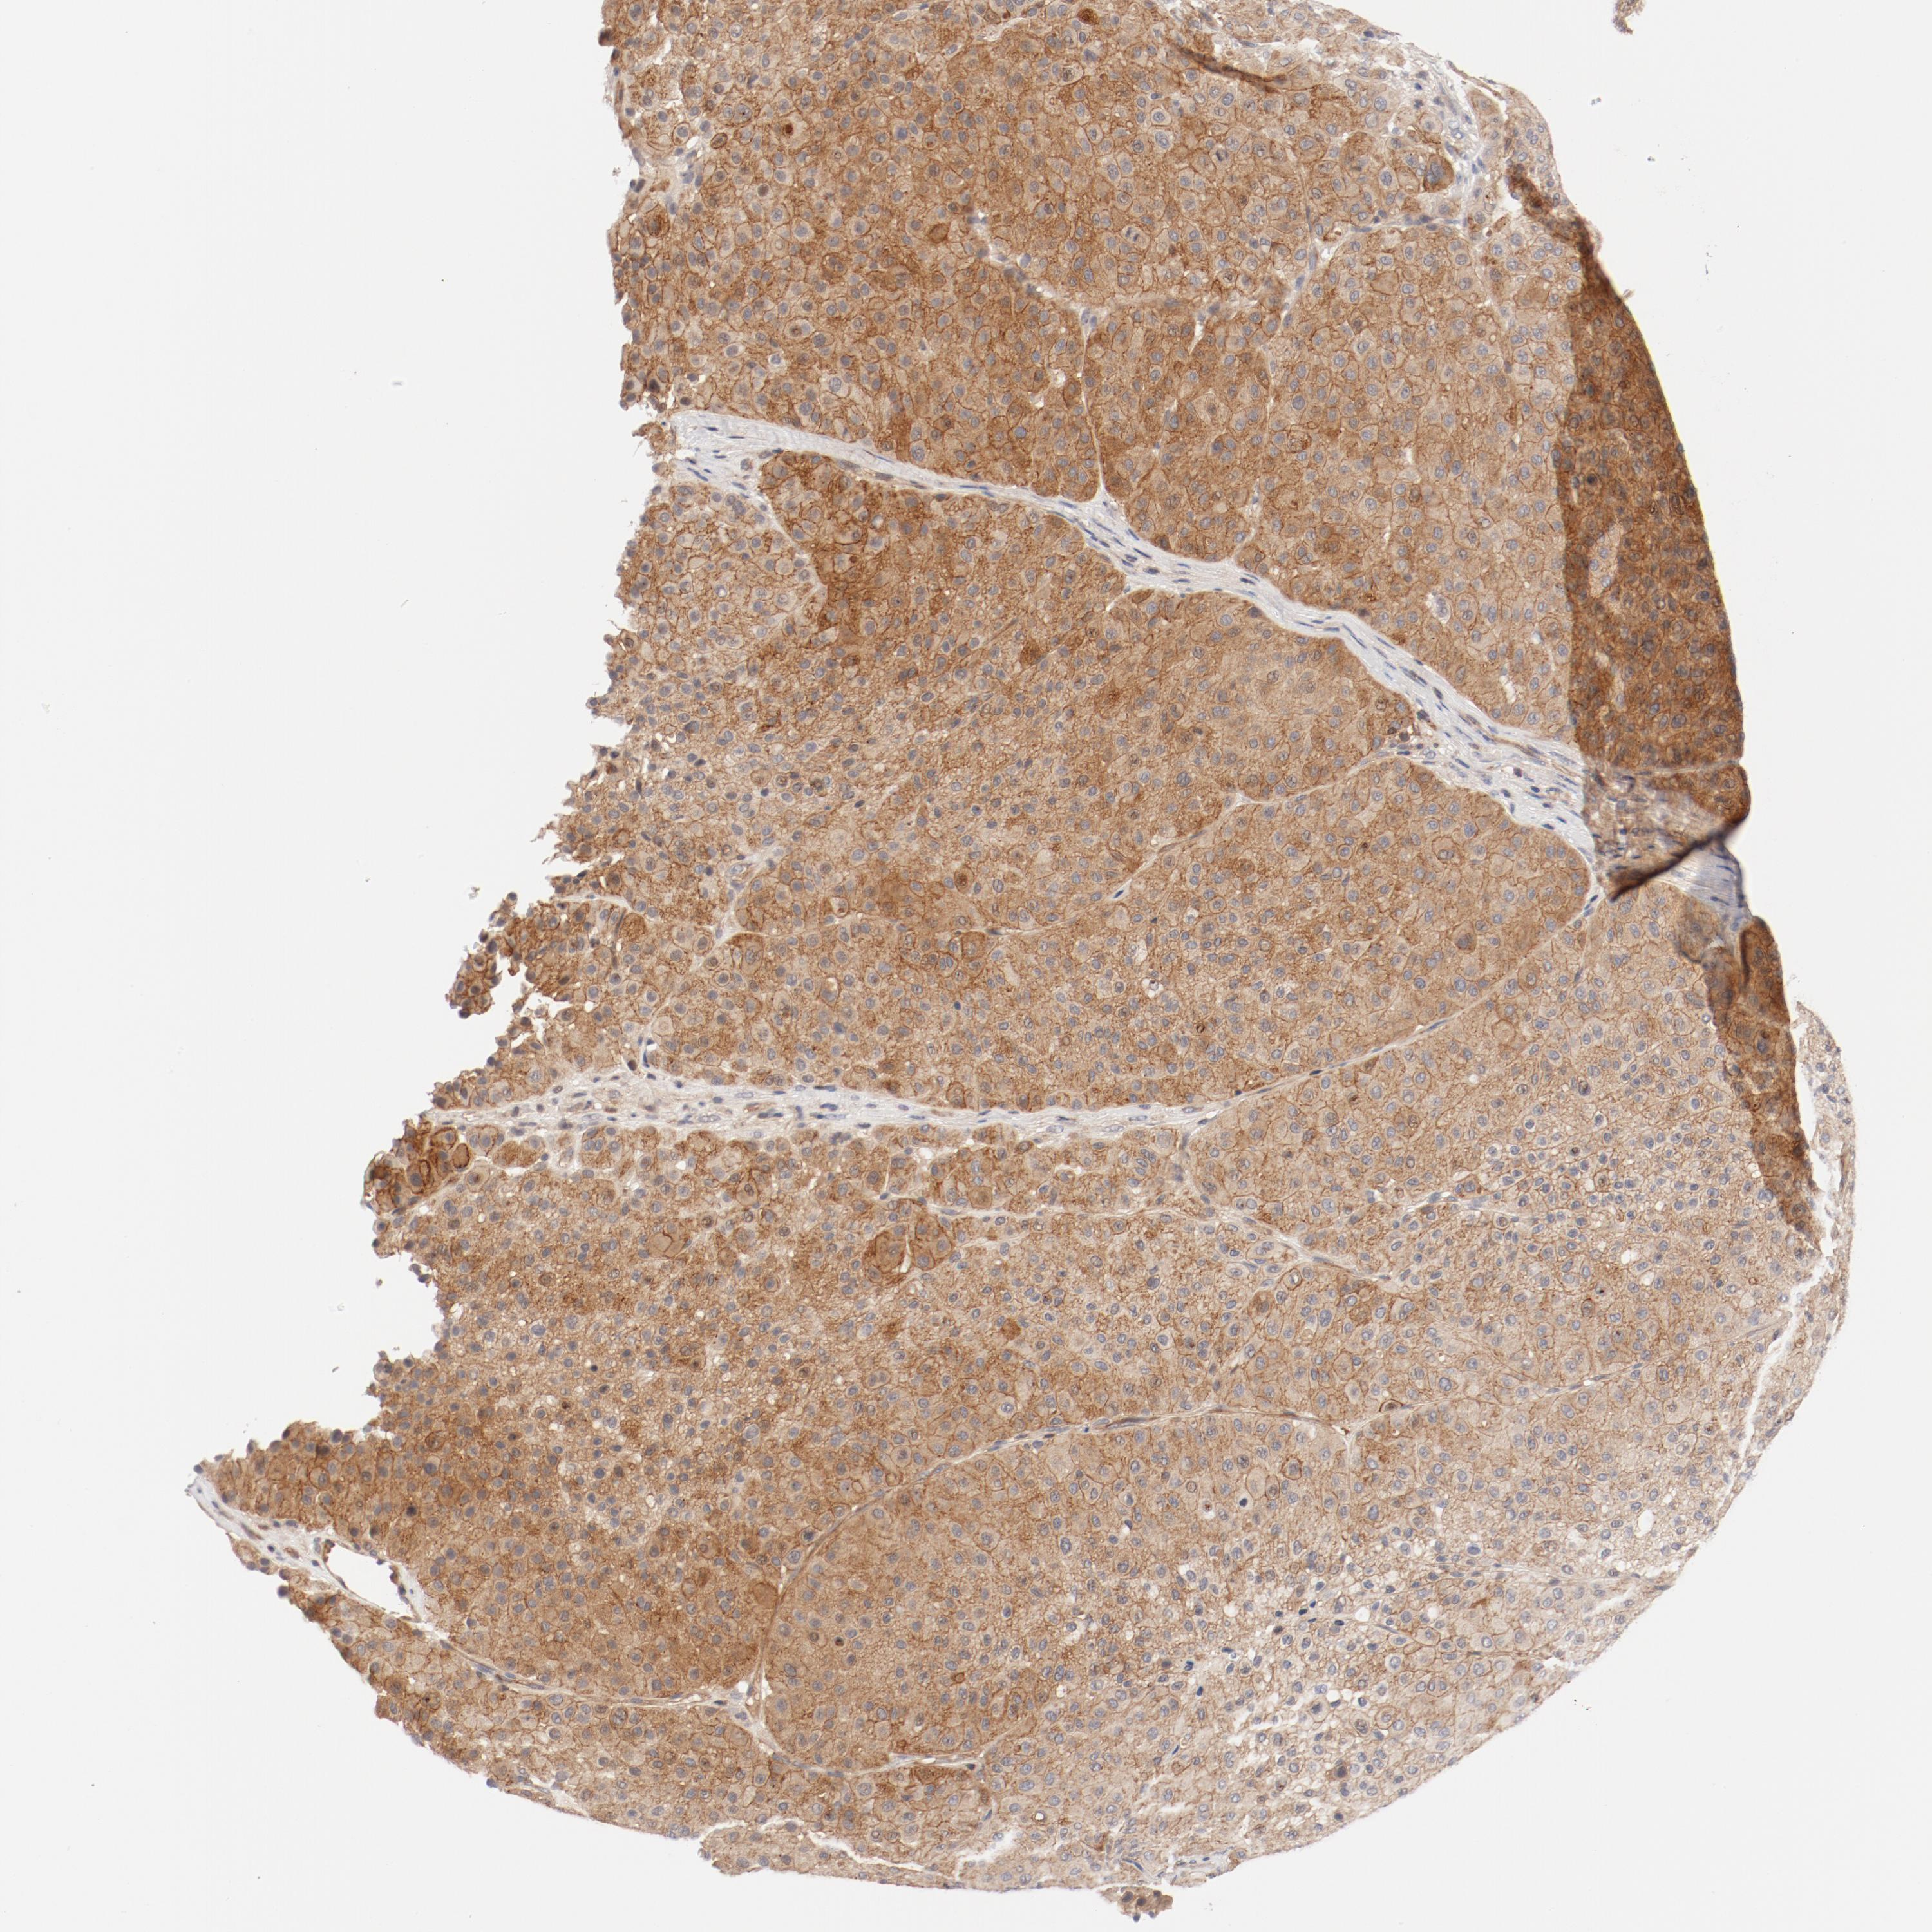

MELANOMA - Protein expressioni

A mouse-over function shows sample information and annotation data. Click on an image to view it in a full screen mode. Samples can be filtered based on level of antibody staining by selecting one or several of the following categories: high, medium, low and not detected. The assay and annotation is described here.

Note that samples used for immunohistochemistry by the Human Protein Atlas do not correspond to samples in the TCGA dataset.

Antibody stainingi

Antibody staining in the annotated cell types in the current human tissue is reported as not detected, low, medium, or high, based on conventional immunohistochemistry profiling in selected tissues. This score is based on the combination of the staining intensity and fraction of stained cells.

Each image is clickable and will lead to virtual microscopy that enables deeper exploration of all samples and also displays staining intensity scores, fraction scores and subcellular localization as well as patient and tissue information for each sample.

Antibody HPA003866

Staining

High

Medium

Low

Not detected

Intensity

Strong

Moderate

Weak

Negative

Quantity

>75%

75%-25%

<25%

None

Location

Nuclear

Cytoplasmic/membranous

Cytoplasmic/membranous,nuclear

Malignant melanoma, NOS